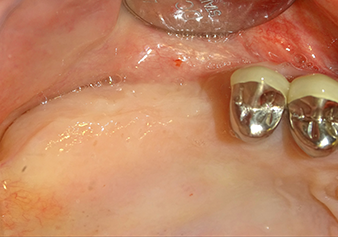

Following an intermediate check (Fig. 4) a further preparation step was performed (Fig. 5). Afterwards, the hydraulic Z35P instrument was used to lift the membrane to the desired position (Fig. 6 and 7). This was followed by further piezosurgical preparation of the implant bed, concluded with a rotary bur and shoulder milling cutter up to the implant diameter of 4.8 mm. Before the implant was inserted, the augmentation material (particle size approx. 0.8-1.6 mm) was introduced underneath the Schneiderian membrane (Fig. 8).